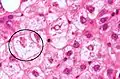

NASH (inflammation) and fibrosis stage 1

NASH (inflammation) and fibrosis stage 2

Lobular inflammation

The primary characteristic of NAFLD is the accumulation of lipids in the liver, largely in the form of triglycerides.[13] However, the mechanisms by which triglycerides accumulate and the reasons that accumulation can lead to liver dysfunction are complex and incompletely understood.[13][28][29][30] NAFLD can include steatosis along with varied signs of liver injury: either lobular or portal inflammation (a form of liver injury) or ballooning degeneration. Similarly, NASH can include histological features such as portal inflammation, polymorphonuclear cell infiltrates, Mallory bodies, apoptotic bodies, clear vacuolated nuclei, microvesicular steatosis, megamitochondria, and perisinusoidal fibrosis.[12] NASH increases hepatocyte death via apoptosis or necroptosis is increased in NASH compared with simple steatosis, and inflammation is a hallmark of NASH.[24]

NAFLD comprises two histological categories: NAFL, and the more aggressive form NASH. The presence of at least 5% fatty liver is common to both NAFL and NASH, but the features of substantial lobular inflammation and hepatocyte injuries such as ballooning or Mallory hyaline only occur in NASH. The majority of NAFL cases show minimal or no inflammation.[2][4][5] Pericentral and perisinusoidal fibrosis occur more often in adult-onset NASH, whereas portal fibrosis is more common in children with the disorder. NASH represents a more advanced stage of NAFL and is associated with poor outcomes such as cardiovascular events, cirrhosis, or hepatocellular carcinoma. ICD-11 does not use the term NAFL as it was deemed confusing with the family of disorders NAFLD. The preferred descriptions are instead: NAFLD without NASH or simple steatosis and "NASH". Also, the modifier with or without fibrosis or cirrhosis completes the diagnostic description.[2][5]